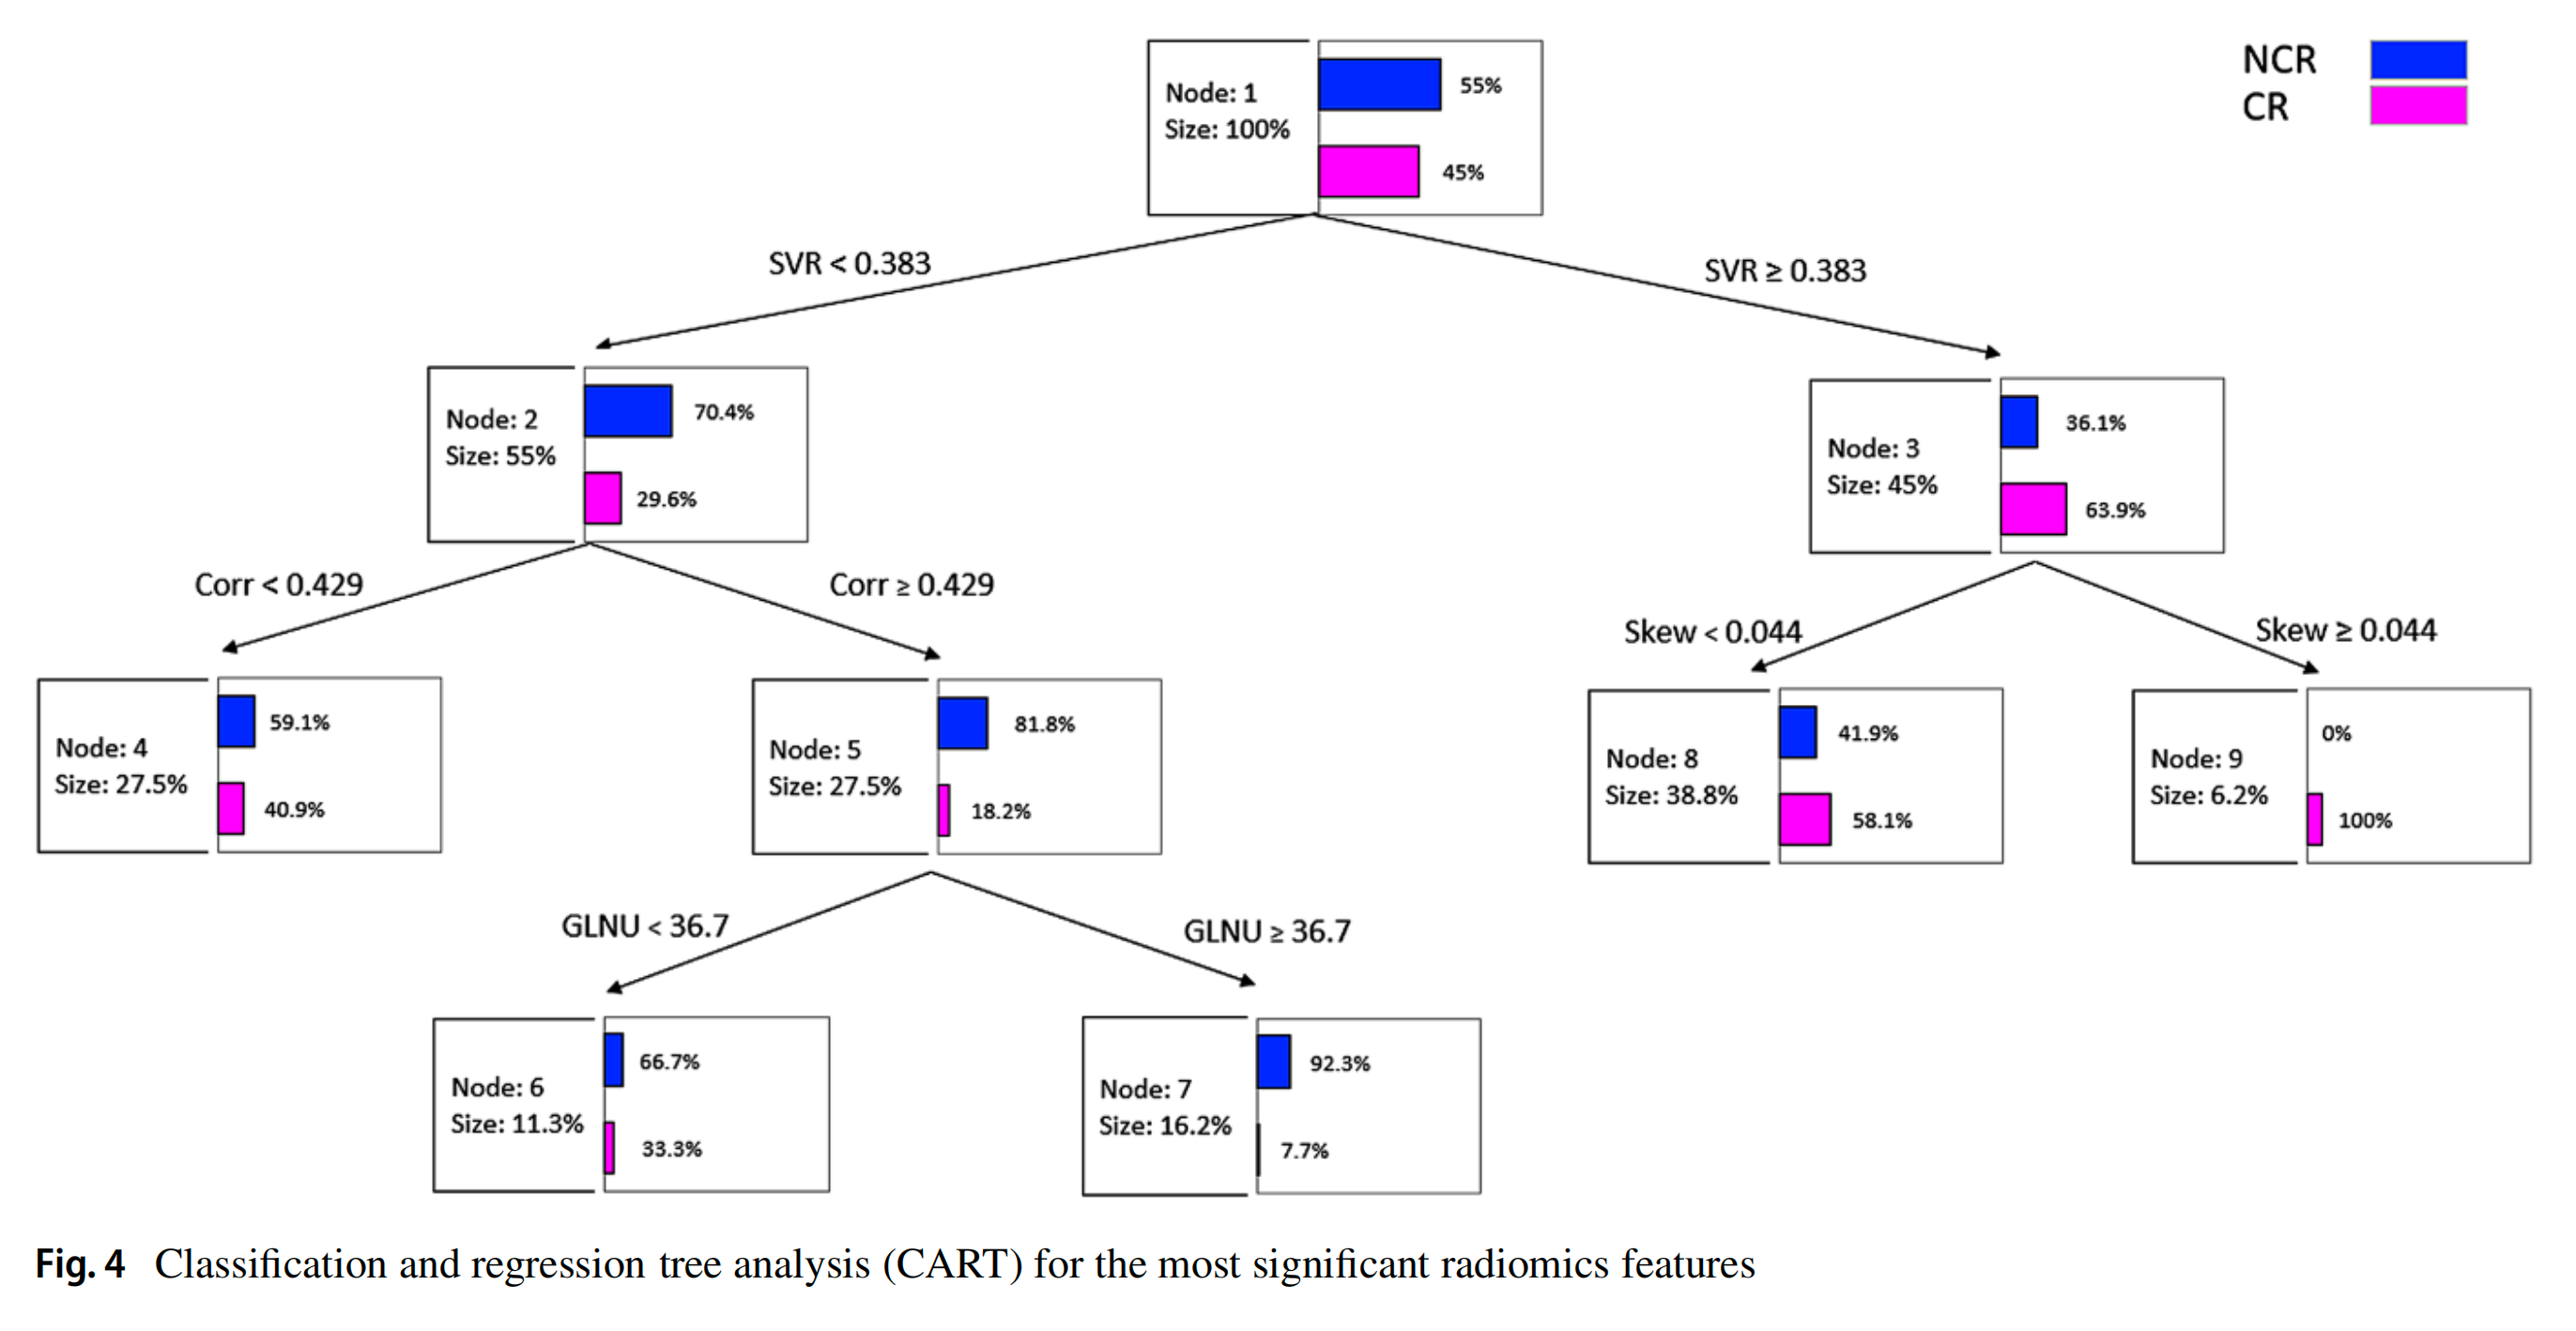

LR和CART模型的分类性能在表3中报告了训练和内部验证数据集。CART分类器表现最佳,准确度、精确度、召回率和F1分数分别为79.2%、78.4%、80.3%和78.5%。

两个模型的接收器操作特性(ROC)曲线交叉验证结果在图3中展示。LR和CART模型的曲线下面积(AUC)分别为0.707(95% CI: 0.633–0.817)和0.753(95% CI: 0.675–0.836)。

Fig. 4 中的分类回归树分析(Classification and Regression Tree Analysis,简称CART)是一种决策树的可视化表示,它展示了如何使用放射组学特征来预测肺转移瘤患者在接受立体定向体放射治疗(SBRT)后的完全缓解(CR)。CART模型是一种监督学习算法,它可以识别出哪些放射组学特征对于区分CR和非CR(noCR)最为重要。

CART模型的决策树通常包括以下元素:

-

根节点 (Root Node): 决策树的起始点,通常基于一个单一的特征进行分割,该特征在所有考虑的特征中对分类结果的预测能力最强。

-

分支 (Branches): 从每个节点延伸出来的分支代表基于特定特征的不同阈值的分割。

-

内部节点 (Internal Nodes): 表示基于某个特征的分割点,每个内部节点都会根据该特征的值将数据分为两部分。

-

叶节点 (Leaf Nodes): 决策树的末端,代表最终的分类决策,即预测的响应类别(CR或noCR)。

-

分割点 (Split Points): 每个内部节点都会根据某个特定特征的值进行分割,分割点是该特征用于区分不同类别的特定阈值。

-

纯度 (Purity): 叶节点的纯度,即该节点下所有样本属于同一类别的程度。纯度越高,表示该节点的预测越可靠。

-

基尼不纯度指数 (Gini Impurity Index): CART使用基尼不纯度指数来评估节点的纯度,并选择最佳的分割点。

CART模型的一个优点是它的可解释性,即人类专家可以相对容易地理解模型的决策过程。通过分析CART图,医生可以更好地了解哪些放射组学特征对于预测治疗反应最为重要,并且可以据此做出更有针对性的治疗决策。

使用这四个顶级特征,我们训练和评估了两个机器学习模型,使用LR和CART分析方法。最佳的诊断性能是由CART分类器实现的,其在训练集和评估集中的准确度、精确度和召回率分别为0.792、0.784和0.803。获得的CART模型具有明显的优势,即易于解释,与机器学习或深度学习的其他方法不同。我们使用四个放射组学协变量,通过九个节点和三个深度级别构建了CART模型,以产生一个直接和紧凑的决策树。CART分析选择SVR大于0.383的病变与完全缓解相关。随后,偏度和相关性在提高病变分类率方面发挥了重要作用,高偏度和低相关值有利于完全缓解。

由于这种高分类准确度,我们认为这个CART模型可能代表了一个有价值的工具,用于放射科医生在为肺部病变制定SBRT策略时选择有效的治疗方案。